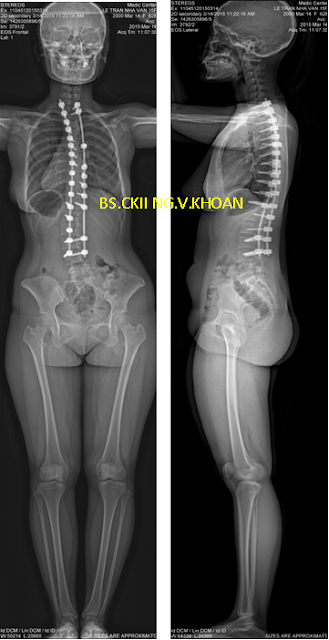

Phẫu thuật gồm việc nắn chỉnh cột sống về càng gần như bình thường càng tốt, bằng dụng cụ ốc chân cung và thanh nối dọc phía sau, và hàn xương để cố định cột sống (thường dùng xương ghép lấy từ mào chậu của chính bệnh nhân). Dụng cụ thường để luôn trong cơ thể không cần mổ lấy ra. Sự phục hồi sau mổ cũng khác nhau tùy từng người. Sau mổ bệnh nhân được truyền máu (nếu mất máu nhiều), truyền dịch, kháng sinh, thuốc giảm đau. Bệnh nhân được khuyến cáo tập ngồi và đi lại càng sớm càng tốt nếu có thể với sự trợ giúp của chuyên viên vật lý trị liệu, để giúp phục hồi sức mạnh khối cơ.

Bệnh nhân được cho chụp X-quang cột sống từ cổ đến khung chậu thẳng và nghiêng để đo độ Cong vẹo cột sống (đo góc Cobb, góc còng lưng, góc ưỡn thắt lưng). Chụp X-quang tư thế nghiêng trái và phải tối đa để dự đoán độ mềm dẻo của cột sống. Nếu phát hiện có các dấu hiệu tổn thương thần kinh, tủy sống, bác sĩ sẽ chỉ định chụp cộng hưởng từ để đánh giá các tổn thương liên quan đến vẹo cột sống.